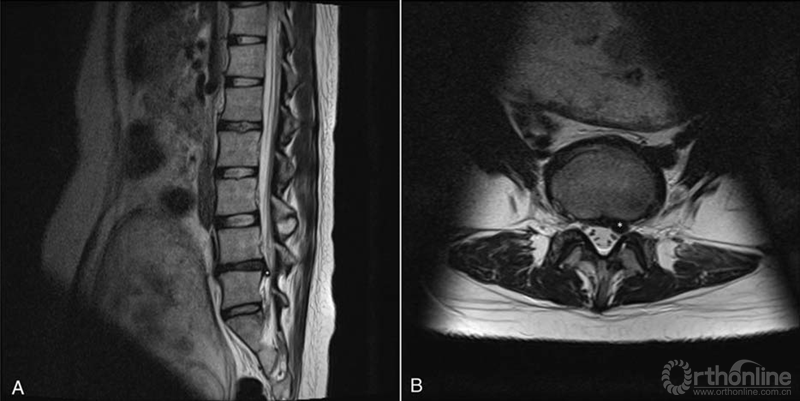

关节背伸肌力减弱(4/5),L5神经根支配区域皮肤感觉迟钝。予以口服乙酰氨基酚(1200mg/d)治疗无效,且症状进行性加重,于20周孕龄时收入院进一步诊治。入院后,腰椎核磁共振(MRI)显示,L4/5节段椎间盘明显突出并压迫左侧L5神经根(图1A,B)。

图1.术前20周孕龄腰椎MRI显示L4/5椎间盘突出(星号)和明确的神经根受压(箭头)(A)矢状位T2加权图像。(B)轴向T2加权像。